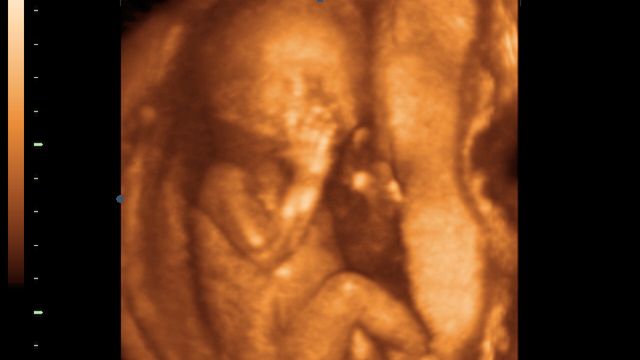

Płód w 11 tygodniu ciąży (zdjęcia 3D)

Główka dziecka nie opada na brzuszek, uwidacznia się podbródek i szyja